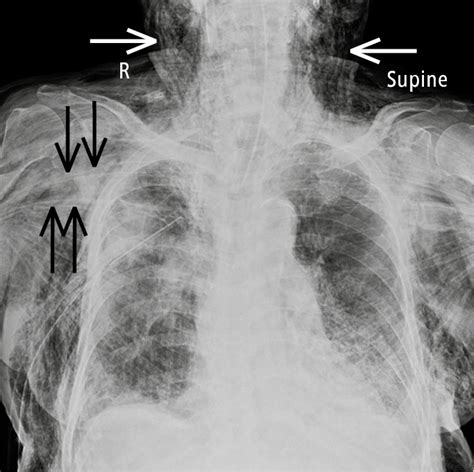

It can be caused by. Web subcutaneous emphysema is a rare condition when air gets into tissues under the skin. It can be caused by. Web surgical emphysema is when gas or air enters the subcutaneous tissue layer of the skin. Web subcutaneous emphysema is when air or gas gets trapped under the skin, usually in the neck or chest area.

Web subcutaneous emphysema is when air or gas gets trapped under the skin, usually in the neck or chest area. Web surgical emphysema is when gas or air enters the subcutaneous tissue layer of the skin. It can be caused by. Web subcutaneous emphysema is a rare condition when air gets into tissues under the skin. Web subcutaneous emphysema is when air or gas gets trapped under the skin, usually in the neck or chest area. It can be caused by.